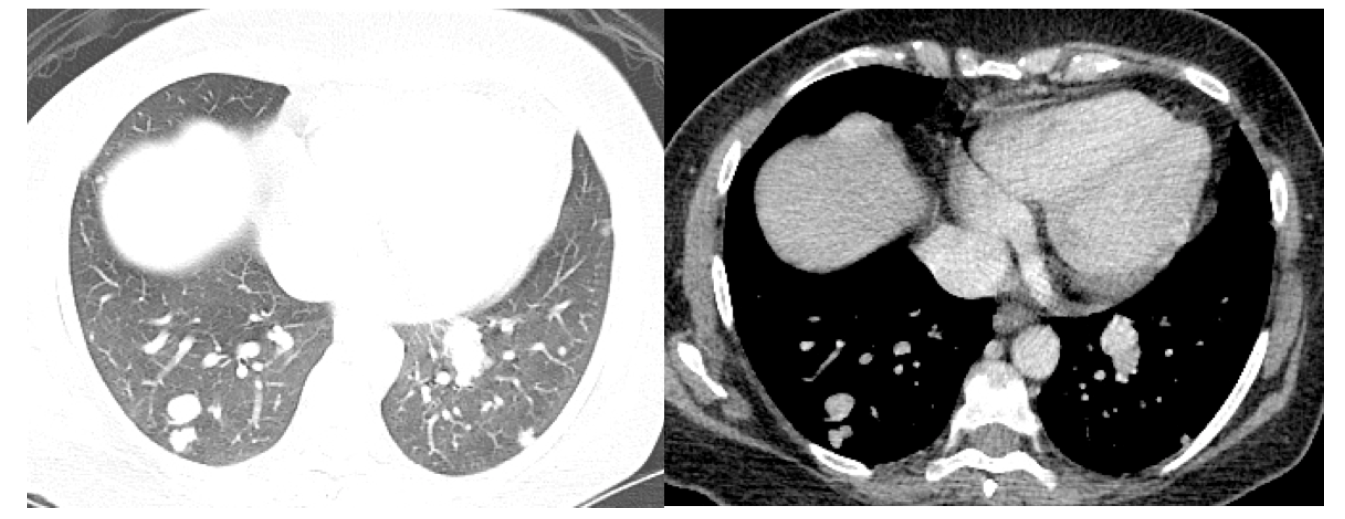

What is this?

Benign nodule